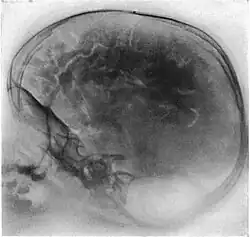

Neumoencefalografía

Una neumoencefalografía (a veces abreviada como PEG) era un procedimiento médico en el cual la mayor parte del fluido cerebroespinal es drenado de la cavidad craneana y reemplazado con aire, oxígeno o helio para permitir que las imágenes de rayos X muestren una mayor definición. Este procedimiento se deriva de la ventriculografía, un método más temprano y primitivo en el cual el aire era inyectado directamente a través de orificios practicados en el cráneo.

El procedimiento fue introducido en 1919 por el neurocirujano norteamericano Walter Dandy.[1]